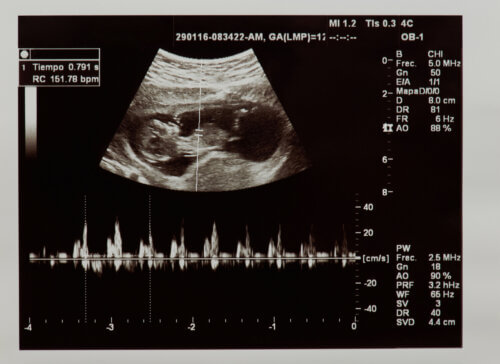

Par fréquence cardiaque, nous entendons le nombre de fois que le cœur se contracte en une minute. Le rythme cardiaque fœtal est identifiable dans les premières semaines de gestation par échographie ou par un moniteur appelé Doppler fœtal.

Dans un premier temps, on évalue si le rythme cardiaque est réellement présent, en vérifiant ainsi la vitalité fœtale. De plus, il est évalué combien de fois le cœur bat pendant une minute. Les valeurs considérées comme normales au stade fœtal se situent entre 120 et 160 battements par minute.

L’évaluation de l’anatomie et de la physiologie du cœur du fœtus peut se faire dans le ventre de la mère. C’est grâce aux échographies réalisées lors des bilans prénataux qui nous permettent d’évaluer, entre autres paramètres, la santé cardiaque et le rythme cardiaque du fœtus.

Certes, au cours du deuxième trimestre, une échographie morphologique est indiquée. Les organes du bébé y sont étudiés en détail. Ici, les structures cardiaques fœtales, telles que les cavités cardiaques, les valves et les vaisseaux sanguins, sont étroitement observées.

Enfin, le fonctionnement du cœur est également évalué ainsi que son mécanisme ou sa conduction. De plus, l’échographie morphologique diagnostique l’existence d’une cardiopathie congénitale pouvant causer des problèmes après la naissance du bébé.